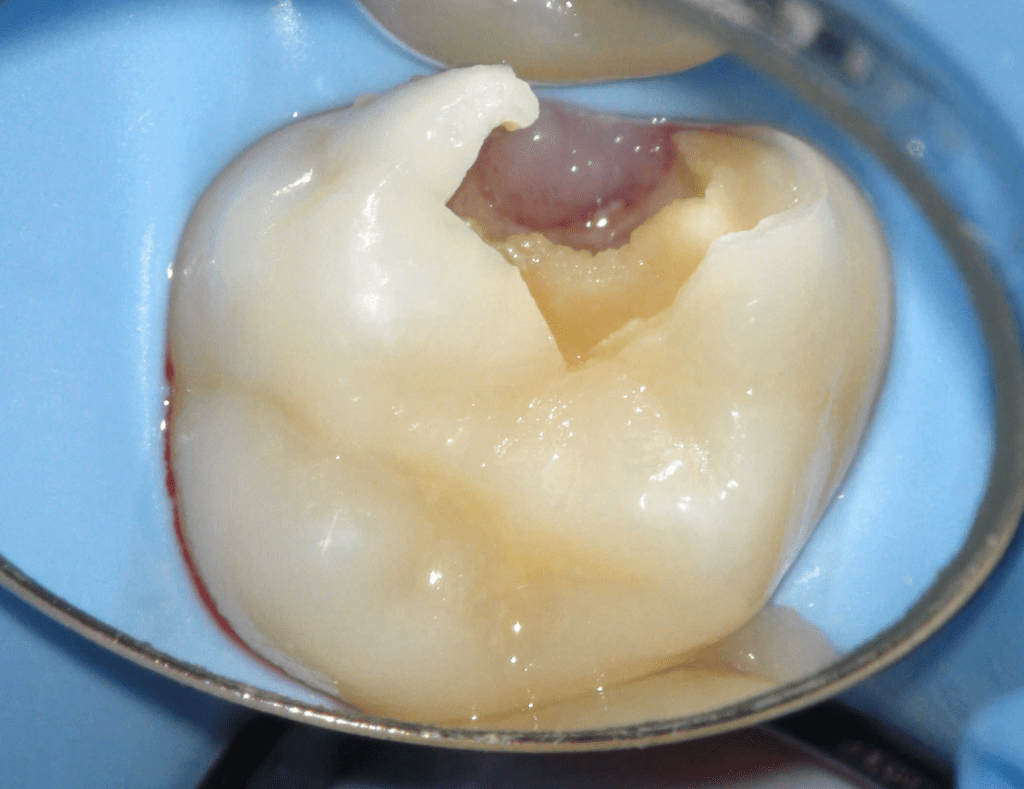

Pulpotomía biodentine + reco preendio